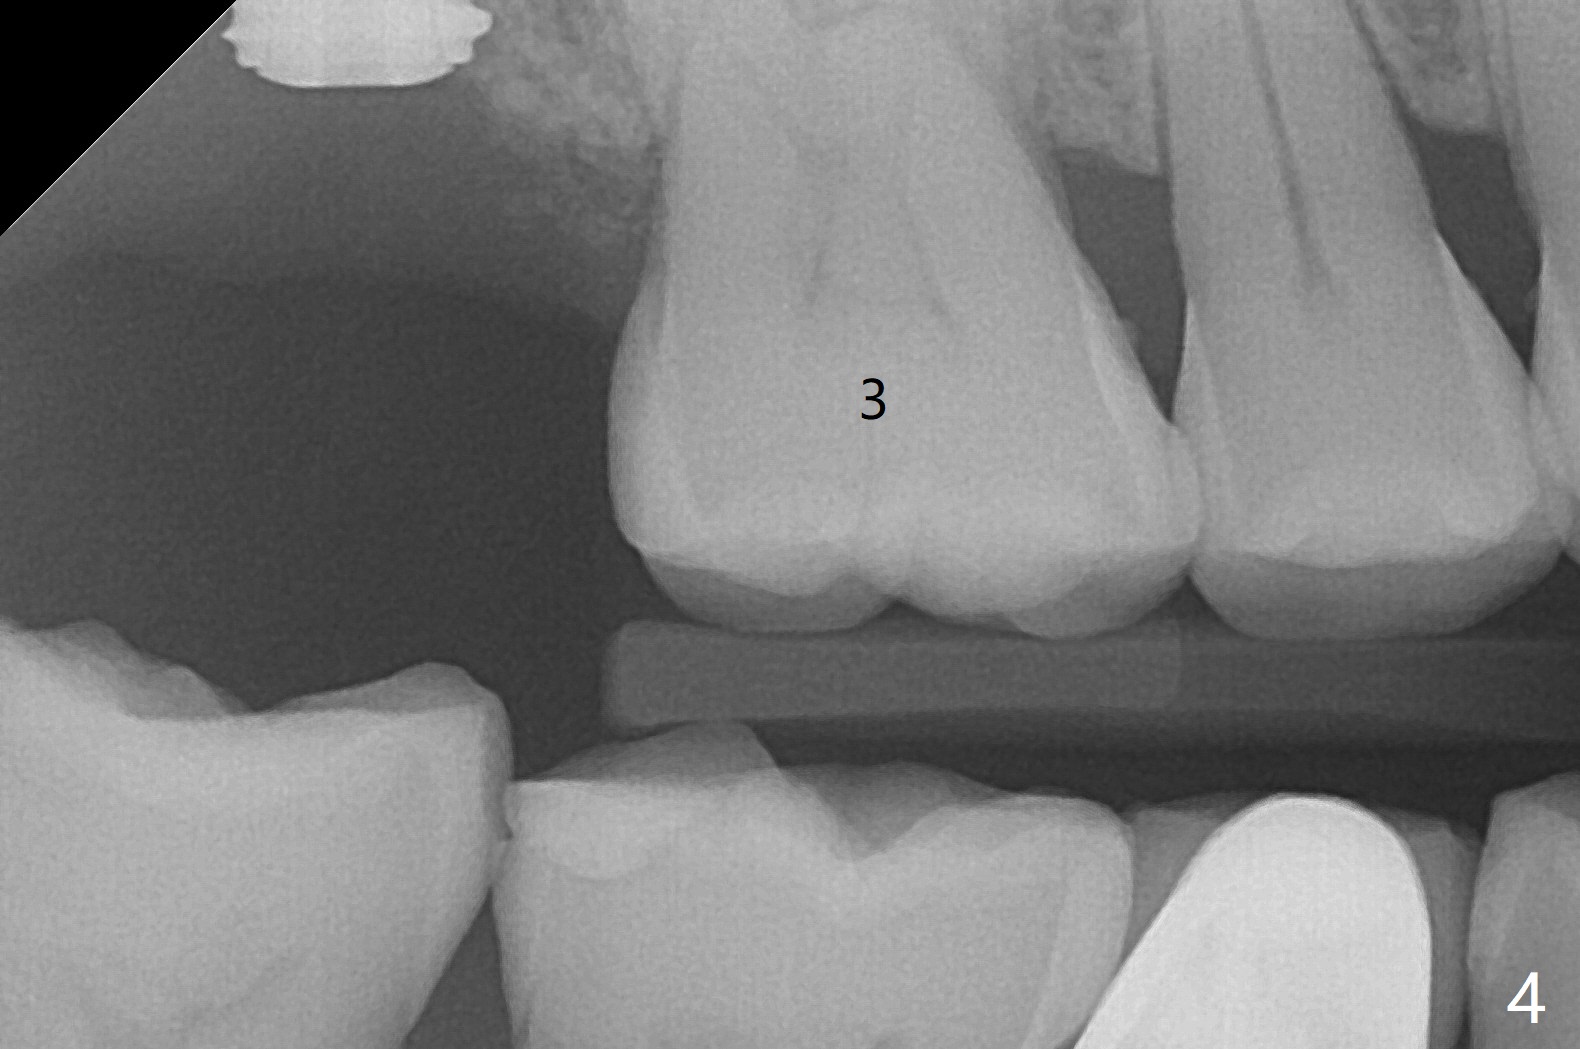

In spite of underprep (4.0x8.5 mm last drill), a 5x8.5 mm implant is placed at #2 with insertion torque ~ 15 Ncm (Fig.1). In addition to the large defect post implant removal with 4.5 month bone graft, he is a heavy gagger with limited mouth opening. Drill cylinders may not engage the metal sleeve precisely. A 5.5x4 mm healing abutment is placed with low emergency profile. The procedure, although difficult, finishes in a timely manner. Otherwise it would be a disaster for the patient and operator. PA taken 1 month postop shows slightly subcrestal placement (Fig.2). When a cemented abutment is placed 4 months postop, there is tenderness. In fact the implant is mobile. A 8x5 mm healing abutment is placed. Nine months postop, the implant remains slightly mobile (Fig.3); a healing screw is placed. The tooth #3 has sign and symptom of crack 13 months postop (Fig.4), related to root fracture of #19 (Fig.5, bruxism). In fact the tooth cracks nonsalvageable post RCT, 9 months post #2 healing screw, 21 months postop. Socket preservation will be carried out with sticky bone and PRF, while #2 implant will be uncovered, followed by placement of a short cemented abutment to hold periodontal dressing. Upper Molar Immediate Implant, Trajectory Xin Wei, DDS, PhD, MS 1st edition 11/27/2018, last revision 07/03/2021